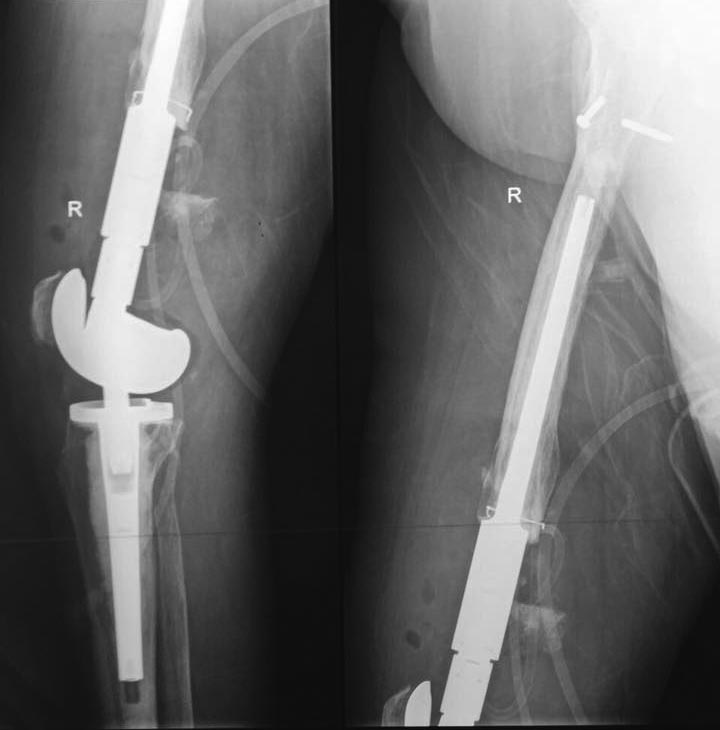

Пациентка 72 года поступила в клинику с диагнозом несросшийся в условиях остеосинтеза перелом н/3 правой бедренной кости, перелом фиксатора ( в анамнезе 3 неудачные операции на бедре по поводу вышеуказанного диагноза). Интересует Ваше мнение по поводу тактики лечения пациентки.

Я думаю, тут надо уже задуматься по поводу протеза коленного сустава, ревизионного (связанного с ножками).

P.s. ножка в бедро должна быть удлиненная, чтоб играла роль штифта.

Иван Валентиныч, дорогой, мне кажется, тут можно и нужно убрать гвоздь, открыв перелом. Сделать декортикацию, вскрыть запаянный канал, рассверлить где нибудь до 12-13 диаметра. Ставить ретроградный полиаксиальный гвоздь. Или смитовский, там хорошие толстые винты, или Stryker, там, если память не изменяет, с угловой стабильностью. Протез первично - против

Здесь вполне можно не вмешиваться открыто. Сделать fixator-assisted nailing. Все закрыто убрать. Хорошо восстановить ось. Через медуллярный канал ручными развертками освежить концы отломков. И заштифтовать. Раз уже был ретроградный стержень - то ретроградно. Я бы взял большеберцовый гвоздь, чтобы ввести винты в разных плоскостях. Ну и гвоздь потолще, и винты 6 мм.

Вот давний пример похожего ложного сустава после неоднократных остеосинтезов.

Александр здравствуйте! Вы представили очень интересный случай, отличный рентгенологический и функциональный результат. Меня смущает только достаточно выраженный гонартроз, как в случае с Вашей пациенткой так и с моей.